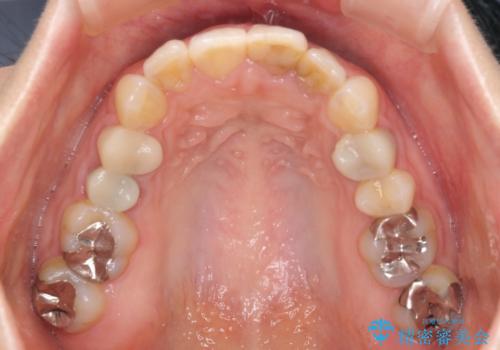

【モニター】前歯のデコボコと奥歯の虫歯 インビザライン治療と奥歯のセラミック治療

- 前歯のデコボコと奥歯の虫歯を気にして来院された患者様です。

主に下顎歯列全体の後方移動とIPR(歯と歯の間を削る)によってデコボコが解消するように設計し、インビザラインにより治療を行うこととしました。

矯正治療後半に下顎左右奥歯をセラミッククラウンにて補綴し、その後インビザラインによる歯列の仕上げを行うこととしました。